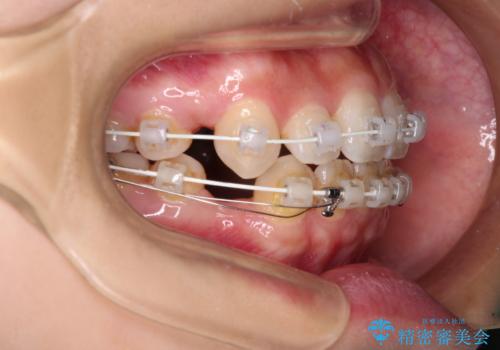

デコボコと八重歯の目立つ前歯 ワイヤー装置による抜歯矯正

- 上下前歯のデコボコと八重歯を気にして来院された患者様です。

叢生を解消する際に出っ歯とならないようにするために、上下左右の小臼歯計4本を抜歯することとしました。

奥歯の咬み合わせが理想的であり、歯の移動に時間のかかる出っ歯でもなかったため、2年程度で治療を終えることを目標としましたが、無事に予定通りの2年間で終えることができました。